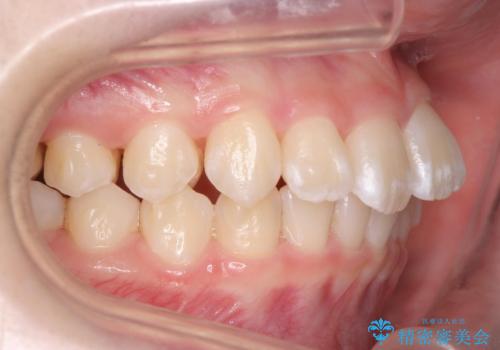

子供の出っ歯 生え代わりと成長期を利用して非抜歯で矯正

- 出っ歯を主訴に来院。

生え代わりを待ってから矯正を始めました。

特に右側のかみ合わせがずれていたため、上の奥歯を後ろに下げています。

下顎も前方に成長し、前歯のかみ合わせも同時に深かったのを浅くすることができました。